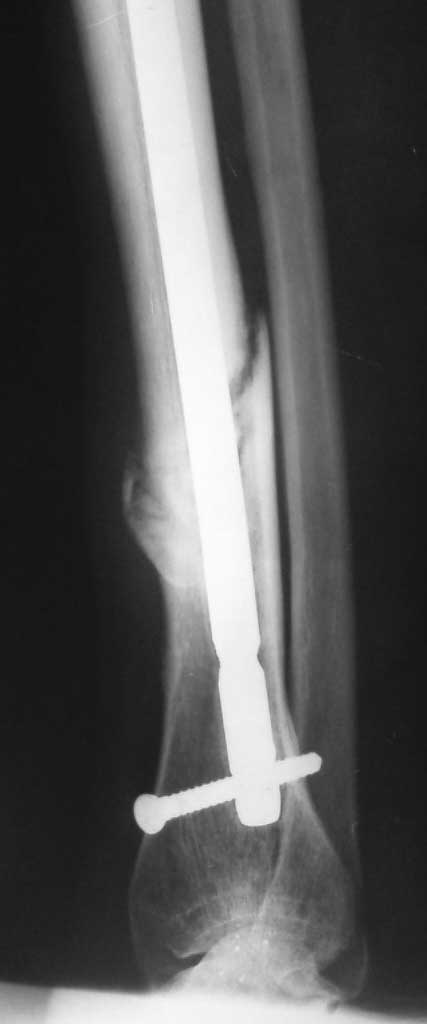

[Ortho] Несращение перелома н\3 б\берцовой кости (ложный сустав)

Пациентка проперирована в марте 2011 года. На Р-граммах несращение. Пробывали давать

нагрузку - появлялись боли в области перелома, опять разгрузка...

Сейчас поступила в стационар. Думаем что делать. Можно конечно убрать стержень и сделать повторный

синтез пластиной с пластикой по Хохутову. Интересна альтернатива!? Все винты в стержне -

статические (проксимально - 2, дистально - 3)